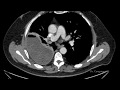

Decortication wikipedia. Decortication is a medical procedure involving the surgical removal of the surface layer, membrane, or fibrous cover of an organ.The procedure is usually performed when the lung is covered by a thick, inelastic pleural peel restricting lung expansion.

Decorticación pleural fundacion argentina del torax. La lesión de la pleura por inflamación (artritis reumatoidea), infección (empiema, tuberculosis), trauma (hemotórax) o tumores, o la acumulación de líquido (derrame pleural) en general purulento o hemorrágico, cuando no se trata a tiempo, puede derivar en un aumento considerable de su espesor que se conoce como paquipleuritis o fibrotórax. Neumol pediatr 2013; 8 (2) 7985 artículo original. 80 contenido disponible en neumologiapediatrica.Cl durante el mismo período. La mortalidad en los niños es mucho menor que en los adultos y en estos últimos constituye un. Toracotomía + decorticación pleural por empiema ~ cirugía ii. Marcelo sandi, cirujano general y de trasplante multiorgánico del hospital universitario "san francisco xavier". En este blog quiero compartir conocimiento, experiencia, dudas y éxitos con todos aquellos a los que les preocupa su salud. Tanto vital. Será dirigido al sitio web del país que usted elija. Ir. Tanto vital. Medicina decorticacion pleural midoctorenlinea.Blogspot. La pileflebitis es una trombosis séptica de la vena porta o de algunas de sus ramas tributarias, la cual es una complicación infrecuente de procesos inflamatorios intraabdominales que además puede acompañarse de abscesos hepáticos. Cholesterol pleural effusion a report of three cases with a. Cholesterol thorax is one of the rare types of pleural effusion, some 60 cases having been reported in the literature. The pleural effusion is characterized by the presence of cholesterol crystals in the fluid, giving it a characteristic satinlike sheen when present in large amounts. Actualidad del motor 20minutos.Es. Más de la mitad de los consumidores pagaría hasta un 20% más por un coche autónomo, según capgemini. Los seis niveles de clasificación de los coches autónomos. Anfac cifra en 30.000 las. Decorticacion pleural youtube. Decorticacion pleural, por el dr. Edgardo noviteÑo. Cirujano pediatrico y general. Por primera vez en buenaventura valle del cauca colombia, / cirugia de torax en pequeÑo lactante de 1.

Grupo f.Tomé concesionario oficial volkswagen audi skoda. Concesionario y taller oficial en madrid volkswagen, audi, skoda y volkswagen vehículos comerciales. Coches nuevos, renting, km0 y de ocasión segunda mano. Patología pleural, modalidad clínicoquirúrgica. Pleural y el cáncer broncogénico. Palabras clave mesotelioma pleural, iatrogenia, pleurotomía, decorticación pulmonar máxima. Abstract it’s alarming the increase of the pleural pathology at worldwide level specially the one due to traumatic and industrial. Pleural effusion traducción al español linguee. Pleural biopsy is usually done to determine the cause of a collection of fluid around the lung (persistent pleural effusion) or other abnormality of the pleural membrane. Choque hipovolémico abordaje y tratamiento en urgencias. Recuerda que si en la valoración del estado de consciencia se obtiene un glasgow igual o menor a 8, tu paciente tendrá que ser intubado. 4. Restablece volumen. La primera medida terapéutica en el choque hipovolémico es el restablecimiento del volumen intravascular y con ello de la precarga. Decorticación pleural por videotoracoscopía toraxclinic. El fin de semana se realizó una una cirugía de decorticación pleural por videotoracoscopía por el equipo de tóraxclinic en. Como consecuencia de una infección pleural antigua o de una hemorragia pleural por traumatismo u otra causa, se puede formar una corteza fibrosa sobre la superficie del pulmón que le impide ventilar adecuadamente y reduce su volumen, con lo que se llega a un. Libre eleccion sanitaria. Cirugía compleja (tipo bentall) de válvula aórtica y aorta ascendente cirugía compleja (tipo bentall) de válvula aórtica y aorta ascendente. Decorticación pleural fundacion argentina del torax. La lesión de la pleura por inflamación (artritis reumatoidea), infección (empiema, tuberculosis), trauma (hemotórax) o tumores, o la acumulación de líquido (derrame pleural) en general purulento o hemorrágico, cuando no se trata a tiempo, puede derivar en un aumento considerable de su espesor que se conoce como paquipleuritis o fibrotórax. La decorticación pulmonar en el empiema pleural. Original. La decorticación pulmonar en el empiema pleural. Pulmonary decortication in the pleural empyema. Orestes noel mederos curbelo, i juan carlos barrera ortega, ii alexis cantero ronquillo, iii josé manuel da costa, iv carlos oliva anayav i doctor en ciencias médicas.

Letra e diccionario de términos sanitarios opossanidad. Tronco o tallo cerebral. Diencéfalo tálamo, hipotálamo e hipófisis. El tronco cerebral controla la digestión, la respiración y el latido del corazón. The benefits of digital chest drainage in pleural. Objective. The aim of this study is to compare the effects of prolonged air leak between the digital chest drainage (dcd) system and the classic drainage system in patients with empyema class iib or iii (american thoracic society classification) in pleural decortication patients. Decortication pleural effusion slideshare. Decortication pleural effusion decortication of the lung is indicated for the condition known as pleural effusion. Pleural effusion is defined as the accumulation of excess fluids between the pleural layers which are the visceral and the parietal layers. Empiema pleural sact.Ar. 1 empiema pleural 1) generalidades / definicion empiema significa acumulo de pus en una cavidad del cuerpo, cuando no se acompaña de la palabra, que especifica la región anatómica, se sobreentiende que. Empiema pleural. Empiema pleural esquema de tratamiento empiema pleural (ep) se define como la presencia de líquido purulento en el espacio pleural. Este proceso infeccioso compromete en su evolución a la pleura y al espacio pleural pudiendo haber o no infección del parénquima pulmonar asociada.